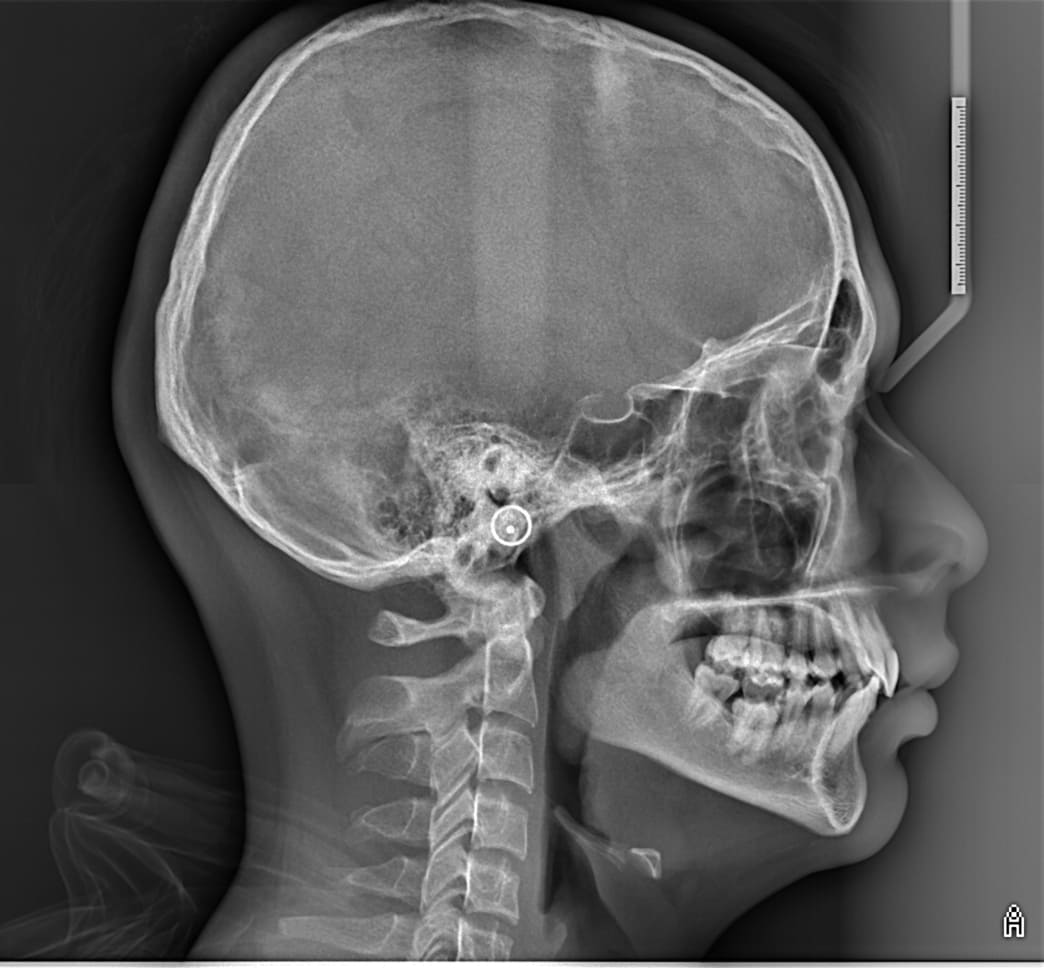

Especialistas en radiografías dentales y maxilofaciales

En OdontID utilizamos equipos de última generación. Nuestros servicios están diseñados para apoyar de manera eficaz a los profesionales de la odontología en el diagnóstico preciso y el tratamiento adecuado de cada paciente.

En Odont ID, proporcionamos radiografías digitales y tomografías 3D para diagnósticos precisos y tratamientos optimizados.